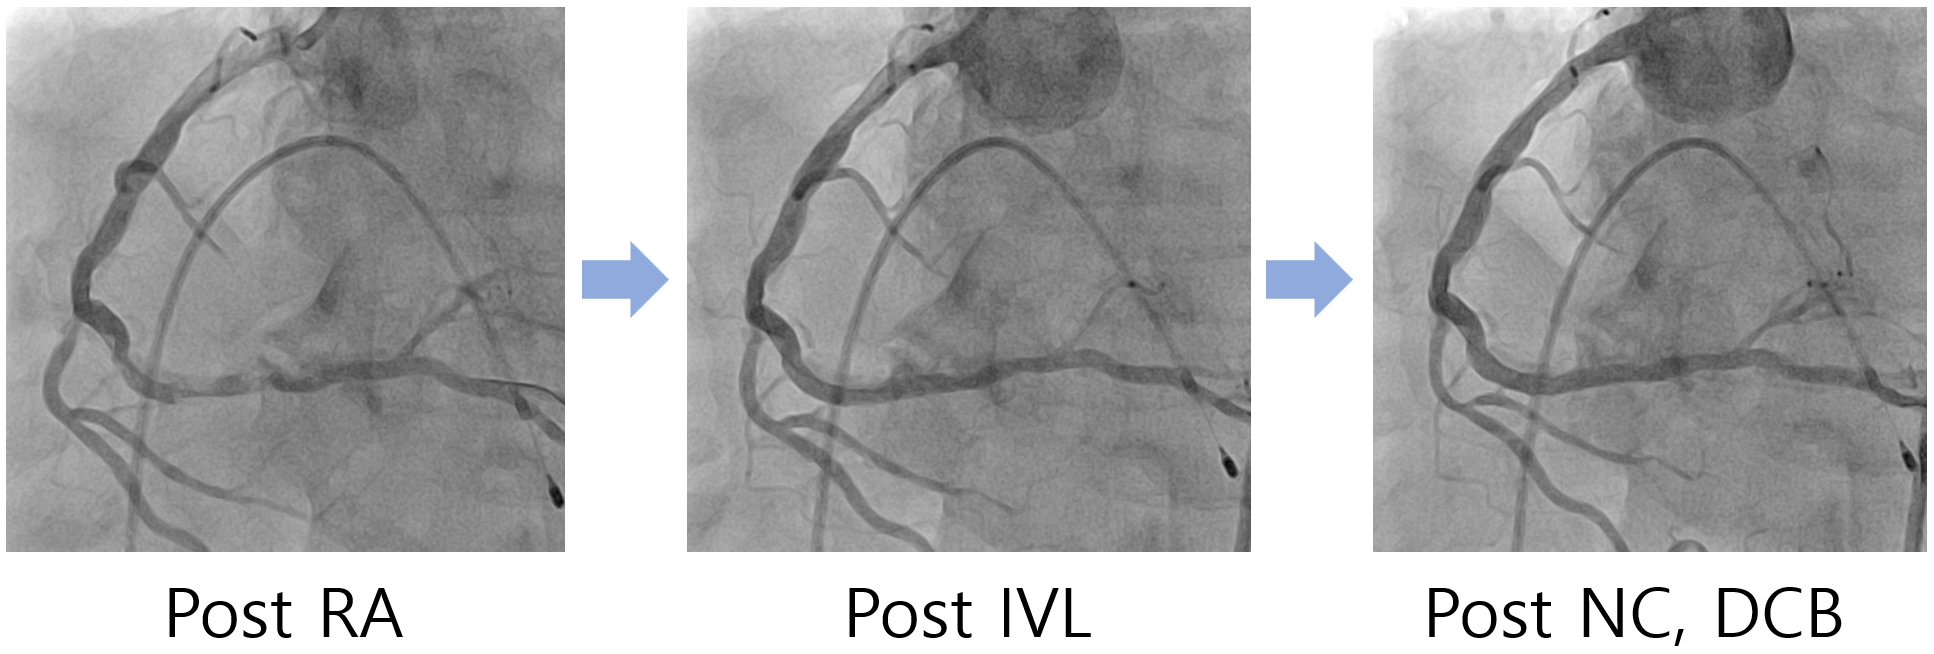

Coronary angiography demonstrated a heavily calcified, diffuse long disease in the mid to distal RCA. Initial intravascular ultrasound (IVUS) could not be advanced across the lesion due to the severe calcification. Without predilation with a non-compliant balloon, rotational atherectomy (RA) was performed using 1.25 mm and 1.5 mm burrs. Post-RA IVUS revealed circumferential (270¡Æ–360¡Æ) encircling calcium with some cracks, but lesion preparation was considered suboptimal.Subsequently, intravascular lithotripsy (IVL) was performed with a 3.0 ¡¿ 12 mm balloon, delivering 12 pulses to the segment that remained resistant to expansion. Follow-up IVUS demonstrated deep calcium fractures and an increase in the minimal lumen area (MLA) from 2.94 mm©÷ to 5.12 mm©÷. Angiography after IVL showed significant improvement in both flow and luminal narrowing.To further optimize the result, additional dilatation with a 3.5 ¡¿ 15 mm non-compliant balloon was performed, followed by drug-coated balloon angioplasty using a 2.5 ¡¿ 30 mm balloon. Final IVUS revealed an MLA of 7.5 mm©÷, and angiography confirmed an optimal result with no flow-limiting dissection.